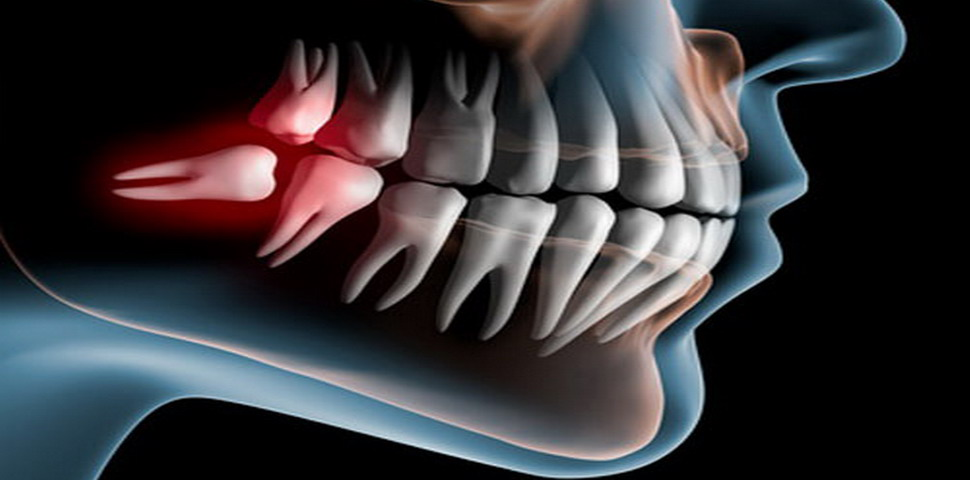

Glavni problemi vezani za umnjake su nemogućnost njihovog potpunog nicanja tj. pojava impakcija ili poluimpakcija tih zuba.

Impaktiran zub podrazumeva zub koji nije nikao, koji se ceo nalazi u viličnoj kosti, zato što mu je normalan put nicanja ometen. Poluimpaktiran zub je zub koji je delimično vidljiv u usnoj šupljini a delimično prekriven mekim tkivom i/ili koštanim tkivom.

Impaktiran zub može da bude bilo koji zub ali najčešće impaktirani zubi su gornji i donji umnjaci, gornji očnjaci, donji premolari, itd. Donji umnjaci najčešće stvaraju komplikacije vezane za impakciju.

Impaktirani zubi mogu rasti u raznim polozajima koji nisu pravilni sa ostalim zubima. U slučaju “dislokacije”, umnjak može rasti u stranu, pritiskajući korene susednih zuba i prouzrokujući velike bolove. Ipak, ako raste daleko od zubnog niza može mirovati i u tom slučaju ga samo treba redovno kontrolisati.

Ovaj ortopan je čest na internetu i na blogovima, od vašeg stomatologa kao i od vaših anamnestickih podataka zavisi da li će se stomatolog odlučiti za vadjenje. Ja lično nekad nisam za vadjenje umnjaka, kao npr na slici, naravno ta odluka zavisi i od godina pacijenta, dubine impakcije. Npr, na slici se vidi da su zubi poredjani u nizu, nema teskobe, čak se vide i razmaci izmedju zuba, a umnjak je totalno prekriven koštanim tkivom, što znači da je infekcija nemoguća. Da bi se izvadio ovakav impaktiran umnjak, neophodna je obilna destrukcija koštanog tkiva, što za posledicu ostavlja ogroman koštani defekt i izuzetno dugačak postoperativni tok ( nekoliko meseci do potpunog koštanog zarastanja).